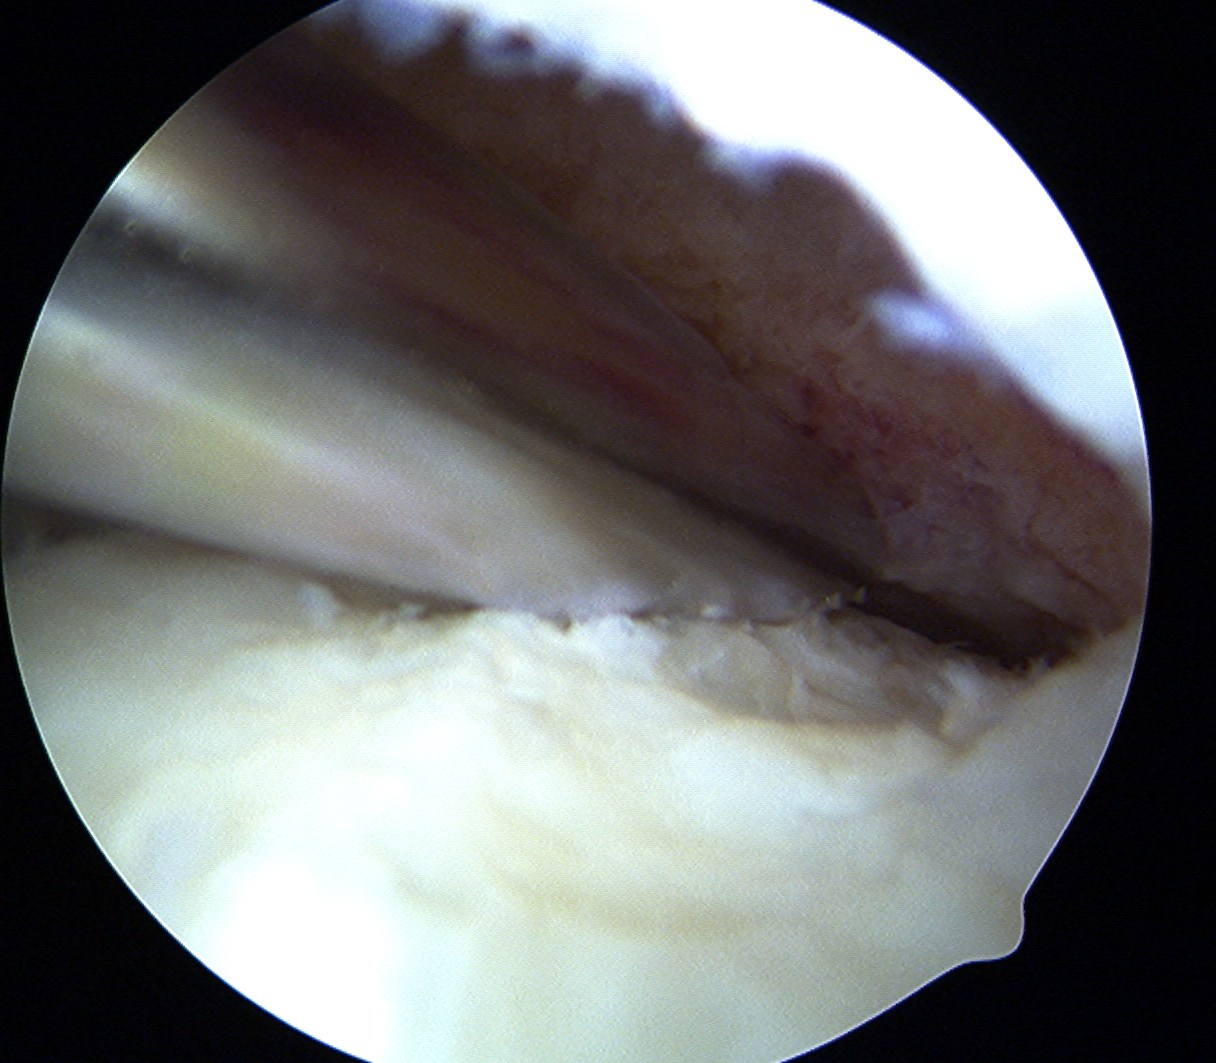

Technique Mosaicplasty Type 3 OCD

Harvest

- insert 4.5 mm chisel

- hammer to appropriate depth / 20 mm

- twist handle to remove

Debride base of OCD and reduce